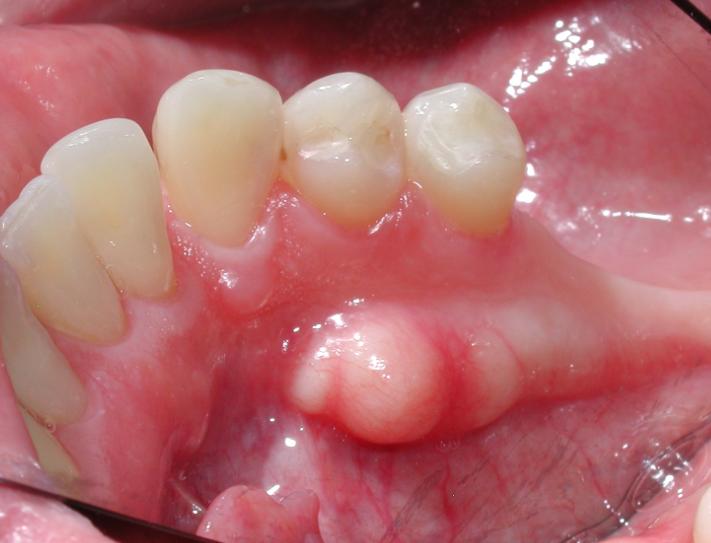

¾Æ·¡ÅÎ ÀÛÀº ¾î±Ý´Ï ºÎÀ§¿¡ Æ¢¾î³ª¿Â »À°¡ °è¼Ó Ä¿Áø´Ù´Â ´À³¦À» ¸¹ÀÌ È£¼ÒÇϽʴϴÙ.

´ë°³ÀÇ °æ¿ì ¾çÃø¼ºÀ¸·Î ¸¹ÀÌ ³ªÅ¸³ª°í ³¯Ä«·ÓÁö ¾ÊÀº µÕ±Ù µ¼ÇüÅ·Π¸¹ÀÌ ³ªÅ¸³³´Ï´Ù.

µå¹°Áö ¾Ê°Ô ÀÔõÀåºÎÀ§¿¡¼ Æ¢¾î³ª¿À´Â °æ¿ìµµ ÀÖ½À´Ï´Ù.

Æò¼Ò¿¡ ´À³¦ÀÌ ¾ø´Ù°¡ Æ¢¾î³ª¿Â ºÎÀ§°¡ À½½Ä¿¡ ¾µ·Á¼ ÅëÁõÀ» ³ªÅ¸³»¸é ÀÎÁöÇÏ´Â °æ¿ì°¡ ´ëºÎºÐÀÔ´Ï´Ù.

À§ÅλÀ¿¡ Àڶ󳪴 °æ¿ì´Â ´ë°³ °æ±¸°³(µüµüÇÑ ÀÔõÀå)ºÎÀ§ÀÇ Á¤ÁߺÎÀ§¿¡ ¸¹ÀÌ ¹ß»ýÇÕ´Ï´Ù.

´ë°³ 2cmÀÌÇÏÀÇ Å©±â·Î ÀÚ¶ó¸ç Æò»ý Å©±âÀÇ º¯È°¡ ÀÖ½À´Ï´Ù.

À§¿¡¼ ¸»¾¸µå¸° °æ¿ì´Â º¸Åë ¸¸Áö°Ô µÇ¸é µüµüÇÑ ´À³¦ÀÌ ÀÖ½À´Ï´Ù.

ÇÏÁö¸¸ Æ¢¾î³ª¿Â °ÍÀÌ ¹°··ÇÑ ´À³¦ÀÌ ³ª°Å³ª ¾Æ·¡Åο¡¼ ¹Ù±ùÂÊ(º¼ÂÊ)À¸·Î °ñÀ¶±â°¡ ¹ß»ýÇÏ´Â °æ¿ì´Â

´Ù¸¥ ÁúȯÀϼöµµ ÀÖÀ¸´Ï ¹Ýµå½Ã Ä¡°ú¿¡ ³»¿øÇϼż °ËÁøÀ» ¹Þ¾Æº¸½Ã´Â °ÍÀÌ ÁÁ½À´Ï´Ù.